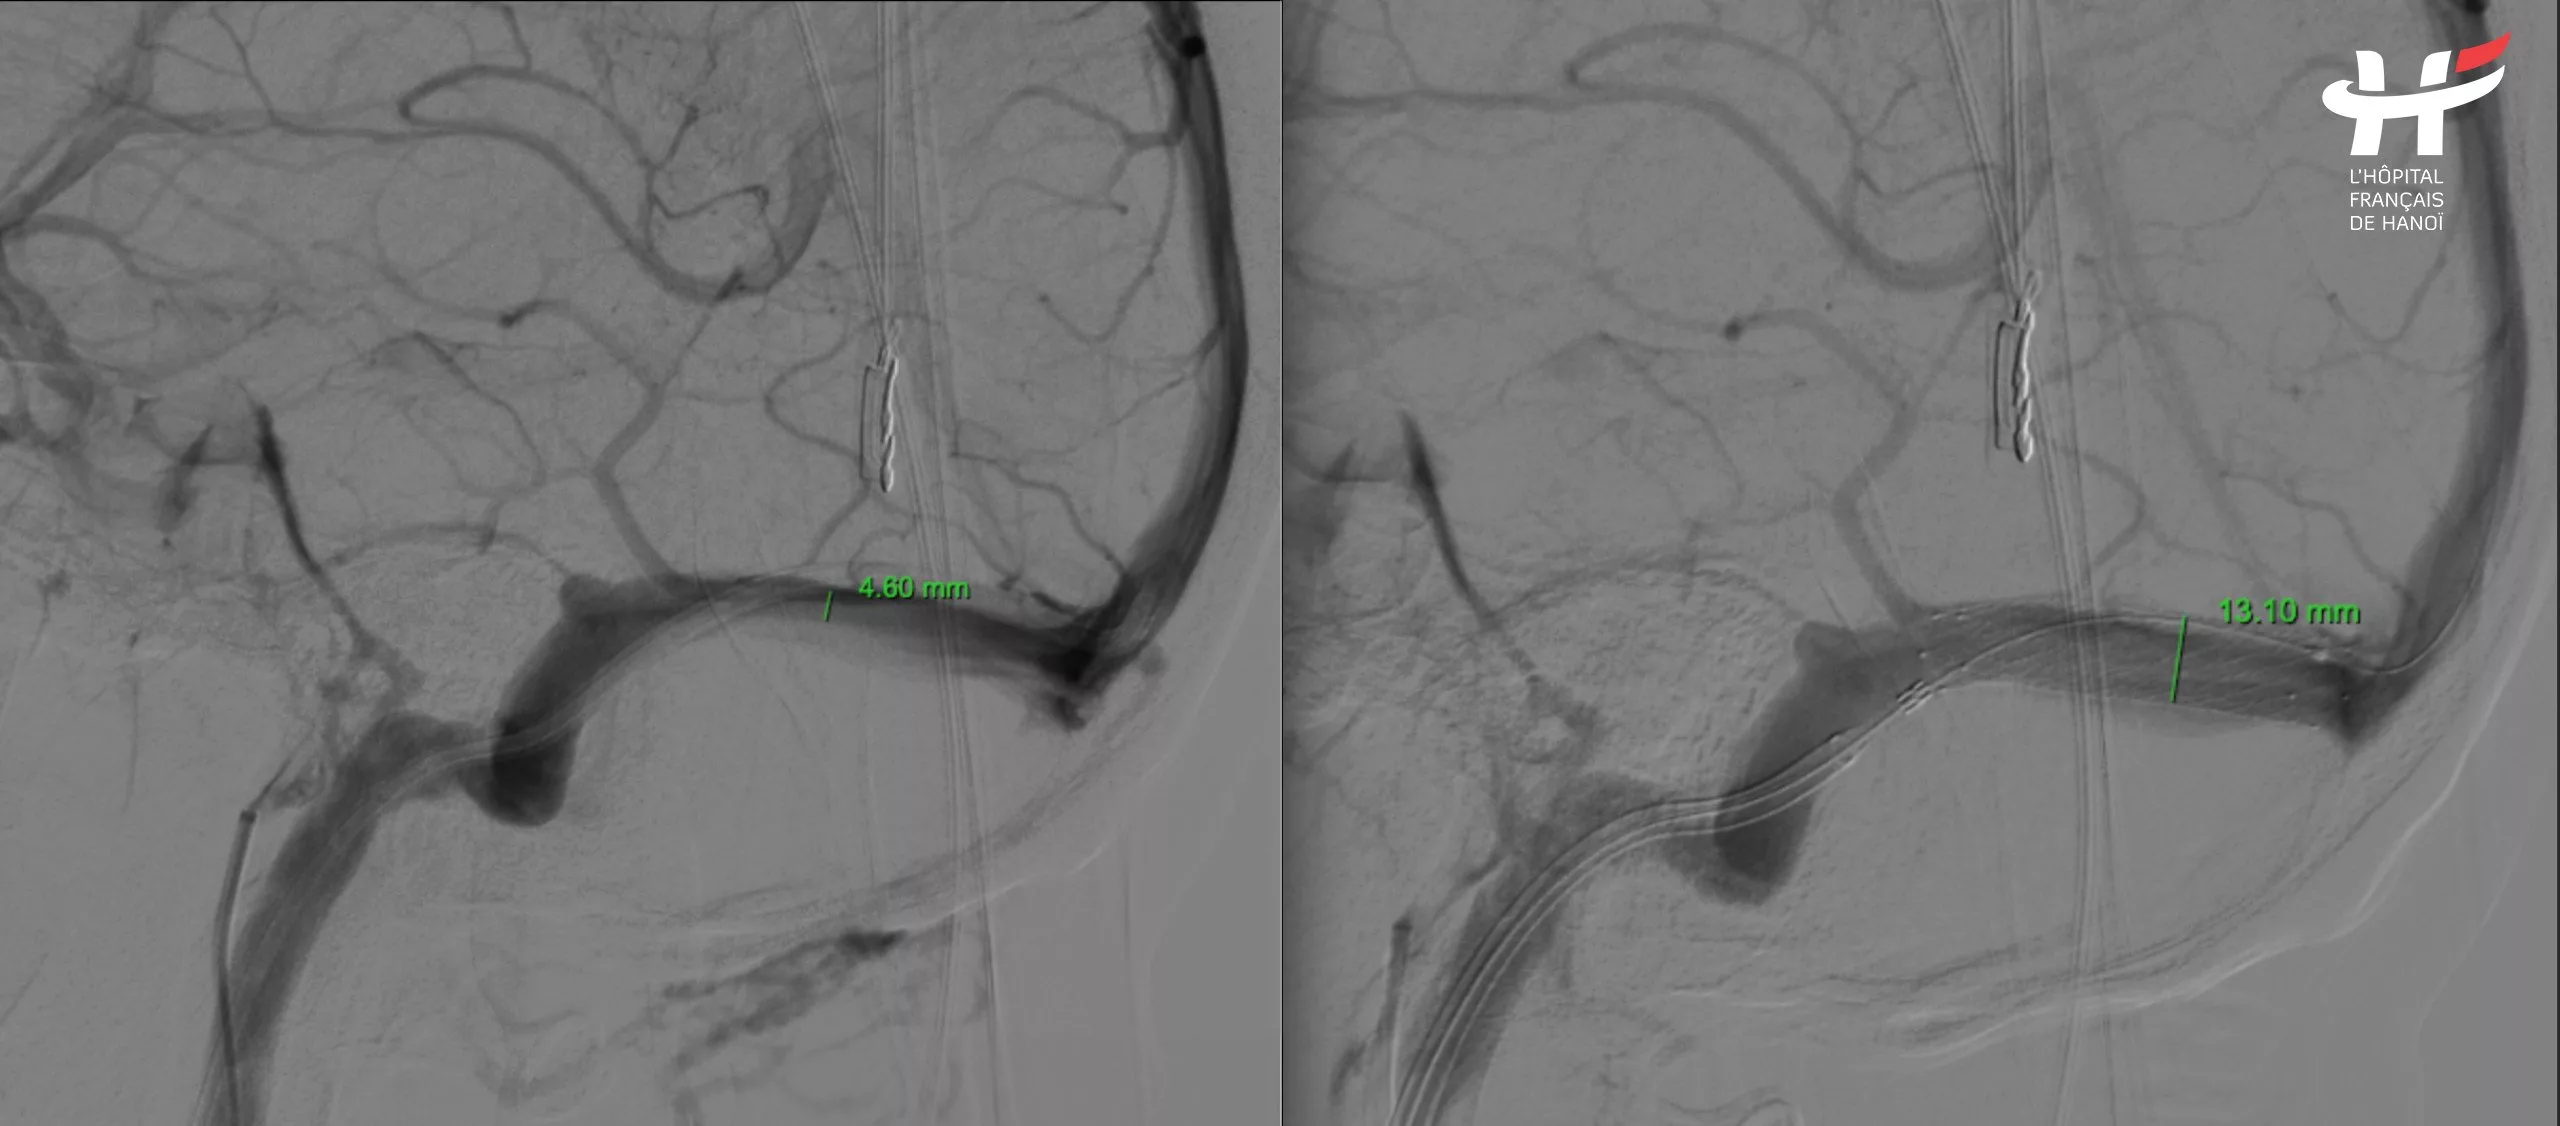

After consulting with these vascular interventional radiologists experts, they could confirm that the patient had a severe right transverse sinus stenosis. This abnormality could explain all the patient’s suffering over the past years. And it was a treatable disease.

After a thorough discussion, the experts decided to place a stent in the patient’s right transverse sinus to clear the obstruction and restore normal blood flow. While arterial stenting is a common procedure for many conditions, venous stenting, particularly within the brain, is extremely rare. Successfully diagnosing the condition was challenging, and the intervention itself was equally difficult.

Secondly, the brain vein in question had a diameter of only 2.3 mm, the same as the catheter used. Additionally, the brain’s blood vessels are not straight but rather twisted and complex. Successfully navigating the catheter through the narrow section was crucial for the intervention’s success.

The intervention involved two main approaches. The first approach was the arterial route. They accessed the artery through the femoral artery, navigating up to the cerebral artery to precisely locate the stenosis. The second approach was the venous route. Simultaneously, they made an entry through the jugular vein in the neck, advancing the catheter up to the brain vein to place the stent.